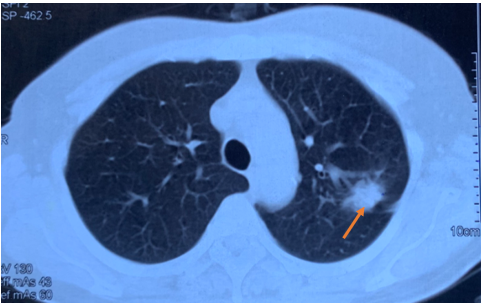

Hình ảnh cắt lớp vi tính lồng ngực tháng 6 năm 2017 khối u thùy trên phổi phải xâm lấn rãnh liên thùy (mũi tên).

Kết quả chụp cắt lớp vi tính (CT) lồng ngực cho thấy khối u thùy trên phổi trái kích thước 20x15mm, bờ tua gai, xâm lấn rãnh liên thùy, kèm theo nhiều nốt mờ rải rác hai phổi, kích thước 5-10mm, phù hợp với tổn thương thứ phát, cùng hạch rốn phổi trái kích thước 10mm.